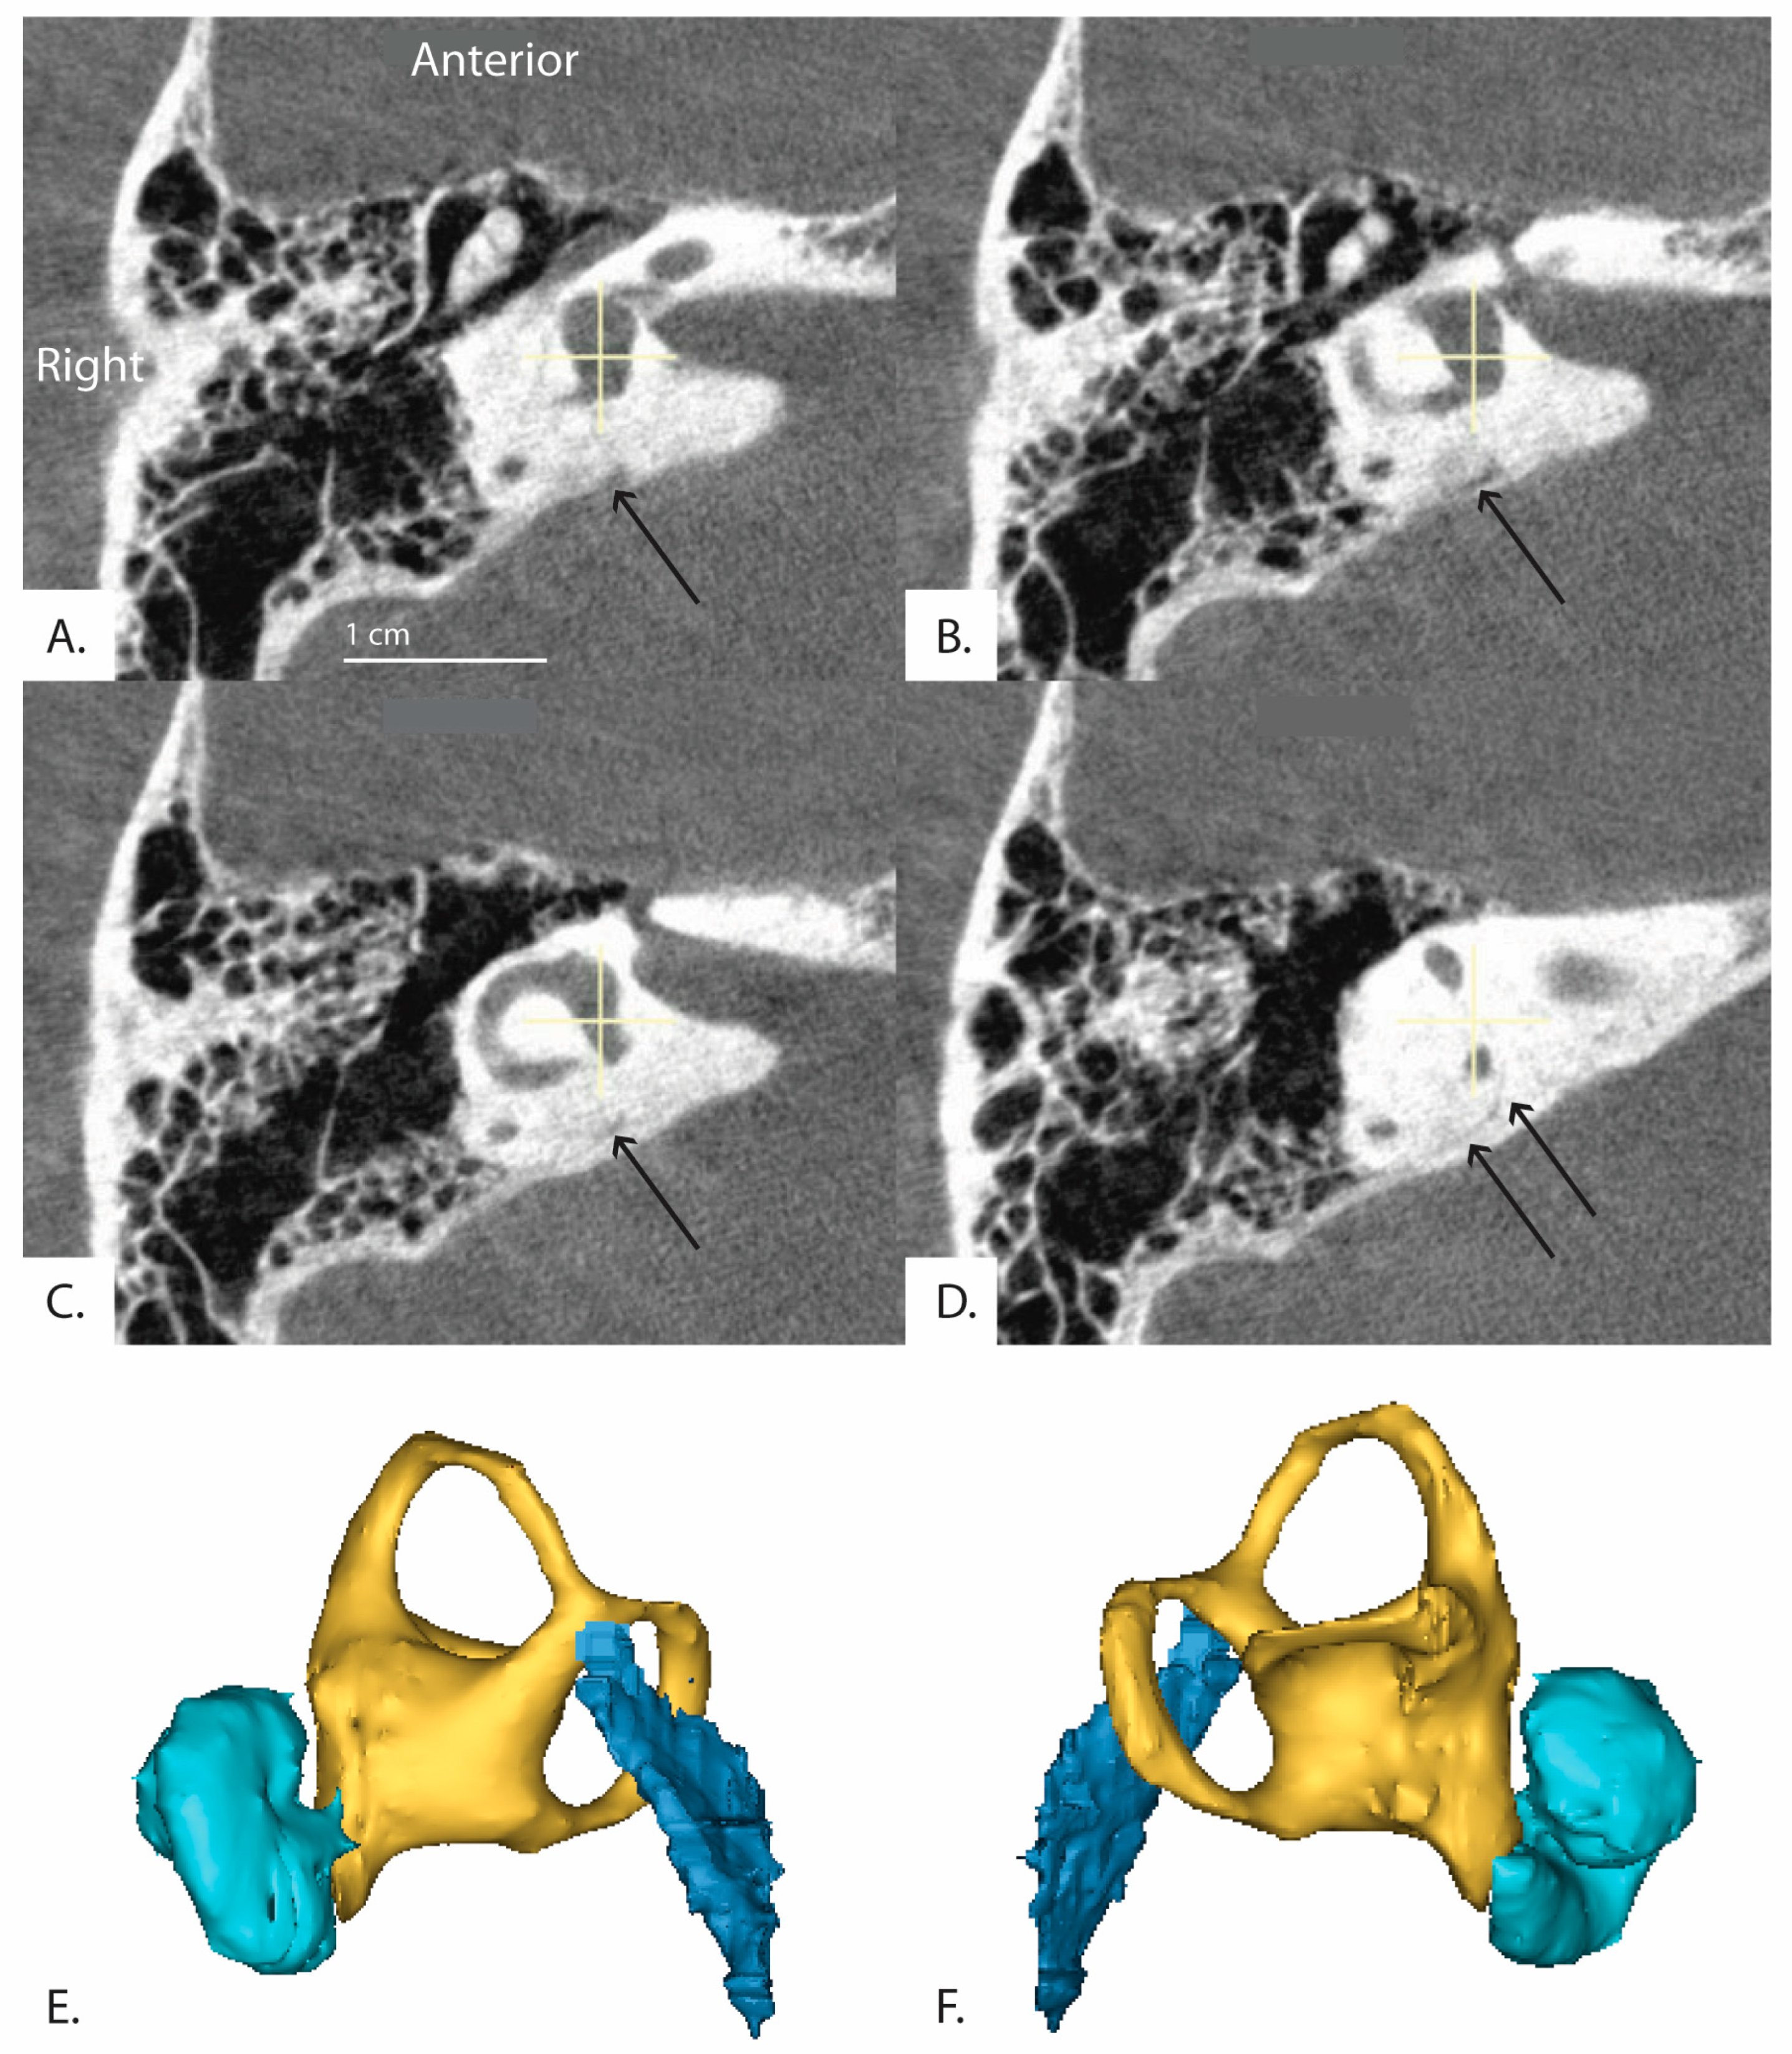

Figure 3.

Box plots show median, interquartile range and outliers for angle of the vestibular aqueduct (ATVA). A cut-off line is shown at 140 degrees for defining abnormal as previously defined. No significant differences in of the vestibular aqueduct was found among Meniere’s Disease (MD), superior canal dehiscence (SCD), superior canal dehiscence syndrome (SCDS), and control groups. In this figure, “Control” refers to patients without diagnosis of MD, SCD, or SCDS.

3.3. ATVA: SCD vs. SCDS

The among patients with a radiologically identified superior canal dehiscence, patients diagnosed with superior canal dehiscence syndrome, and patients diagnosed with Meniere’s Disease were compared. Median and interquartile range values for were not significantly different among the three groups (Patients without MD or dehiscence: 108 (17.4) degrees, n = 407; Superior Canal Dehiscence: 105 (14.3) degrees, n = 32; Superior Canal Dehiscence Syndrome = 105 (16.8) degrees n = 112; Meniere’s Disease = 107 (18.6) degrees, n = 21) (Figure 3). Pairwise comparisons were therefore not performed.

The aim of this study was to determine the distribution of vestibular aqueduct angles in a large population of individuals with a variety of otologic diagnoses and to examine whether other inner ear disorders like SCDS may have a hypoplastic vestibular aqueduct. Nearly all individuals in this study fell within the normal range for the angle of the vestibular aqueduct and 11 had a diagnosis of clinical Meniere’s disease. None of the affected ears of patients with Meniere’s disease in this study met the criteria for a hypoplastic vestibular aqueduct. Furthermore, no significant differences were found in the vestibular aqueduct angles among the patients with Meniere’s disease, patients with solely an anatomic superior canal dehiscence diagnosed on imaging, and patients with superior canal dehiscence syndrome. Among all CT scans, we found 13 patients (14 ears) with a vestibular aqueduct that exceeded the 140 degrees angle cutoff set by Bächinger et al. for patients with hypoplastic Meniere’s disease pathology, yet none of those patients had Meniere’s disease in the affected ear (Figure 3). One of the ears with ATVA > 140 degrees was from a patient with a diagnosis of Meniere’s Disease, but that diagnosis applied to the contralateral ear. Three of the ears with > 140 had a diagnosis of SCDS, and the other 9 ears with > 140 came from patients without Meniere’s disease or dehiscence of the superior semicircular canal. Thin bone was identified over the posterior semicircular canal in two cases. There did not appear to be a consistent pathology identified in individuals with a hypoplastic vestibular aqueduct on CT imaging.